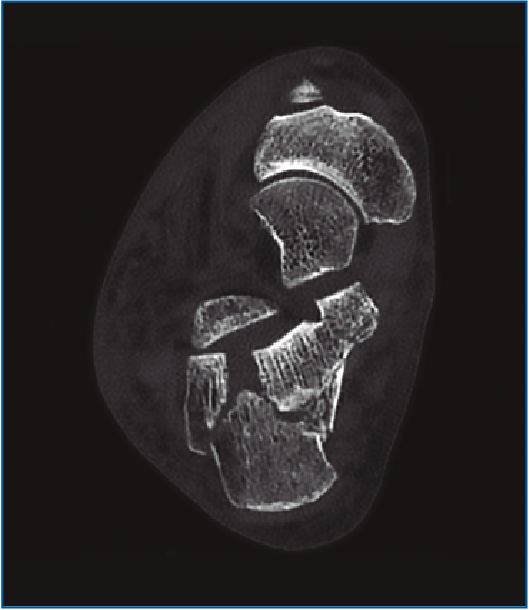

Primero, realizamos limpieza de tejidos blandos y localizamos el flexor hallucis longus (FHL), que será el límite medial de seguridad. Recordamos que, en las fracturas de grado II de Sanders (Figuras 1 y 2), permanece íntegro un gran fragmento anteromedial, mientras que el fragmento posterolateral se desplaza. Tras la limpieza, identificamos la fractura (Figura 3) y movilizamos el fragmento lateral. Luego cambiamos los portales e introducimos el artroscopio por el portal medial, que nos permite acceder hasta el seno del tarso y visualizar el ligamento interóseo talocalcáneo. A través de un pequeño abordaje en la cara lateral del calcáneo reducimos la articulación subastragalina posterior (Figura 4A).

Figura 1. Fractura del calcáneo Sanders IIA.

Figura 2. Fractura del calcáneo Sanders IIB.